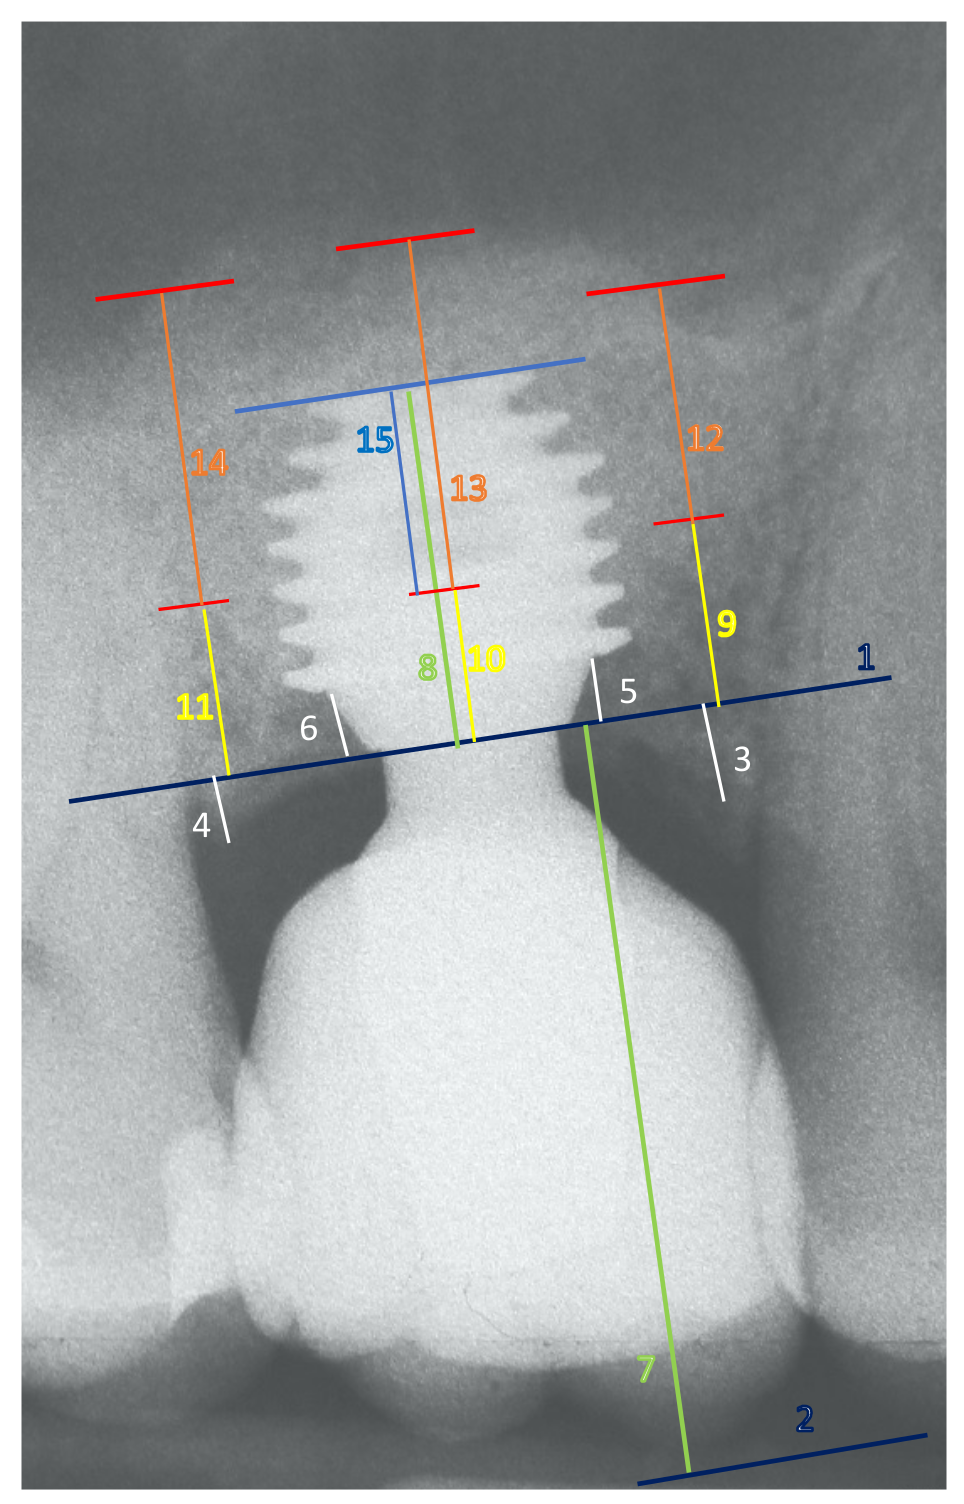

2.5. Study Variables and Outcomes

- -

- Implant protrusion into the sinus (IPS), measured at implant placement as the linear distance between the sinus floor and the implant apex;

- Elevation of the Schneiderian membrane, defined as sinus lift (SL): SL was measured on the mesial, central, and distal point of each implant as the linear distance between the sinus floor and the apical point of the membrane elevation; for each implant, at each examination interval, an average (av) mesial-distal-central value for sinus floor level (av-SL) was calculated;

- Percentages of graft (β-tricalcium phosphate) resorption (GR);

- Cases of Schneiderian membrane perforation (MP).

Appendix A.3. Study Variables and Outcomes

Appendix A.3.2. Peri-Implant Bone Levels and Sinus Floor Level